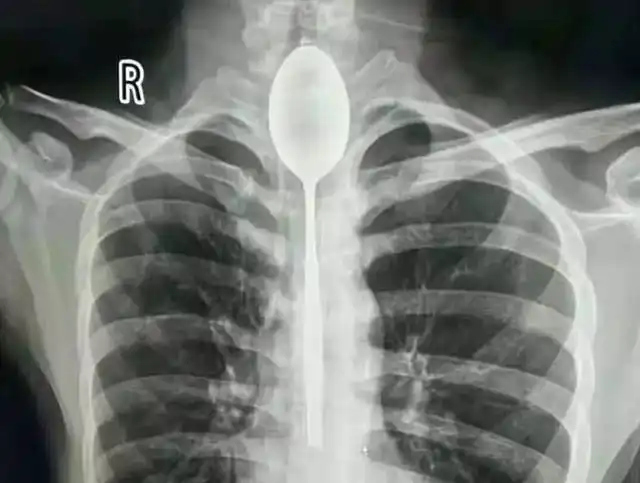

Парень из Китая целый год жил с ложкой,